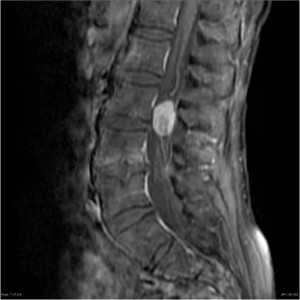

Ганглионеврома конского хвоста. Сагиттальная Т1-зависимая МРТ после контрастирования.